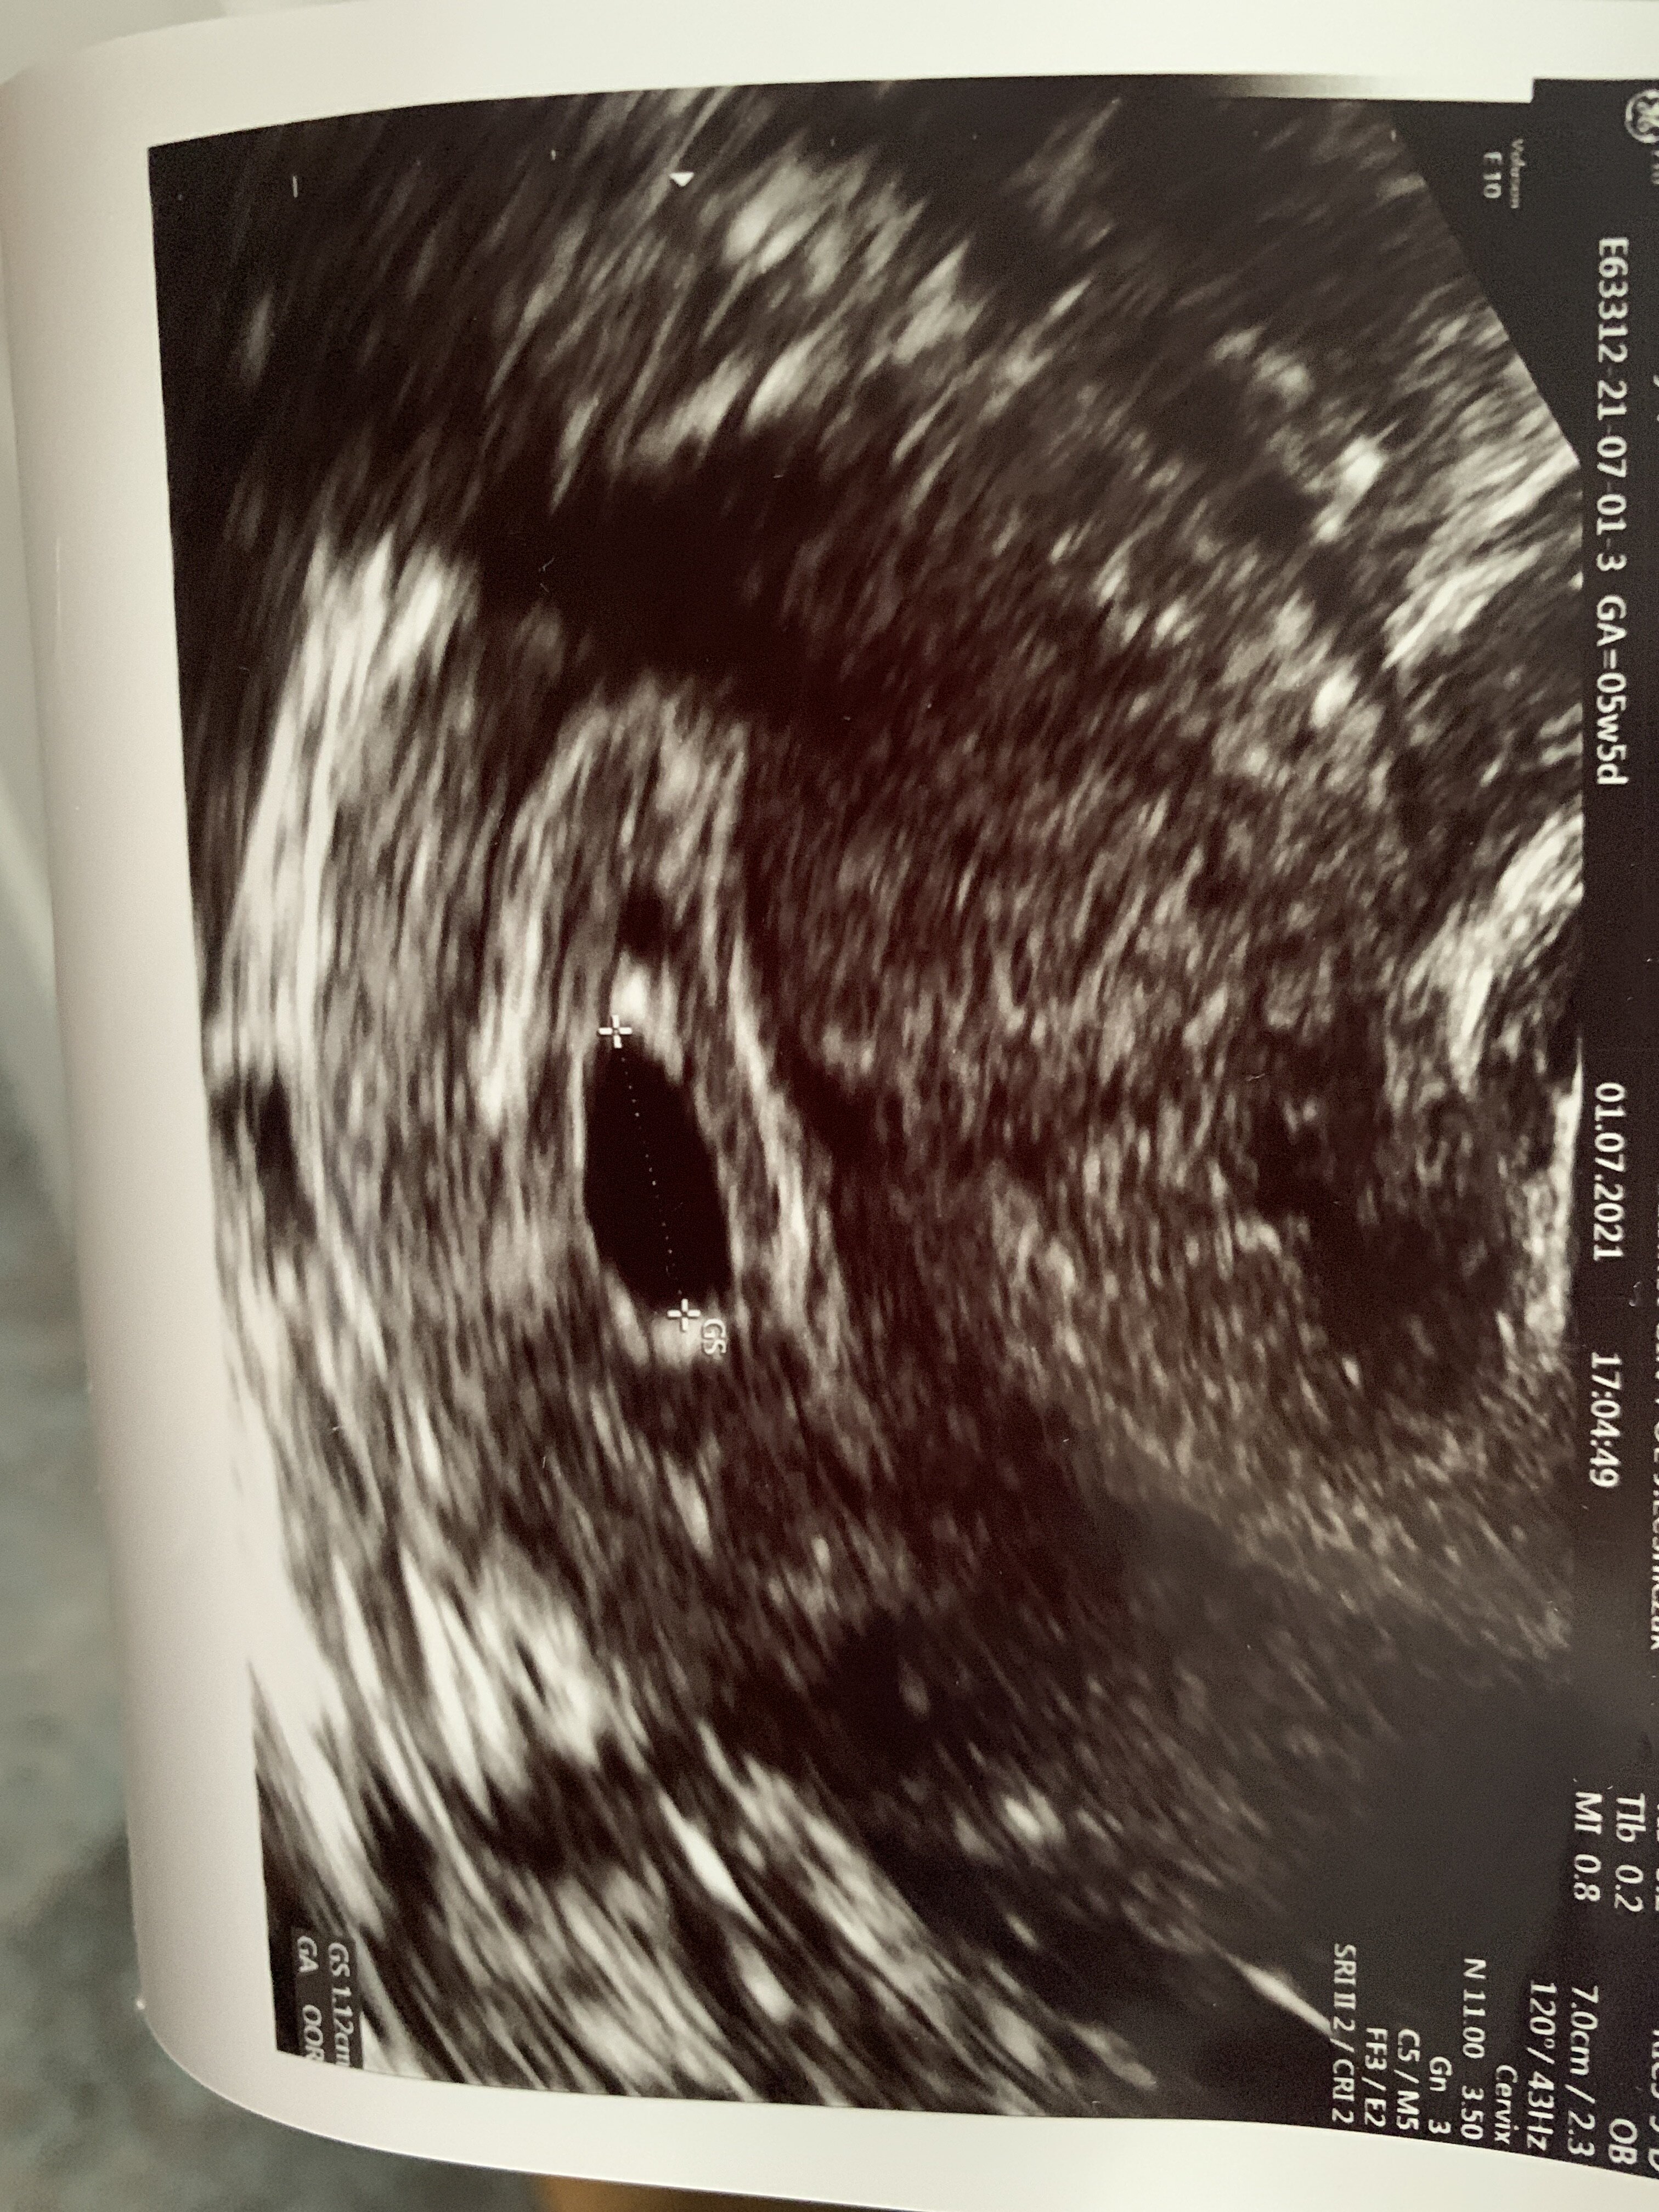

Witajcie, przepraszam ze zalozylam kolejny temat, nigdy nie bylam dobra w wyszukiwaniu czegos na forum. Wczoraj bylam u ginekologa wg om jestem w 5+5 tyg ciazy, na zrobionym usg jest pecherzyk ciazowy 1,12cm bez widocznego zarodka. Kolejna wizyta za 3tyg. Czy oznaczać to moze „pusta ciaze” ? Czy jest jeszcze za wczesnie aby bylo widac zarodek?

• image.jpg

2,2 MB · Wyświetleń: 114